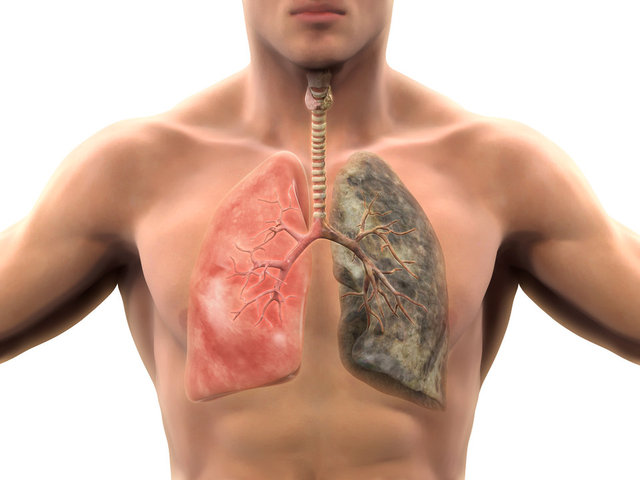

SİGARAYI BIRAKIN

Nur Ecem Baydı Ozman, “Yapılan bilimsel çalışmalar; sigaranın sağlığa zararlarını tartışmasız ortaya koyuyor. Bağışıklık sistemi zayıfladığında enfeksiyonlara yatkınlık artıyor. Bağışıklık sistemini olumsuz etkileyebilecek her faktör bu dönemde özellikle dikkate alınmalı. Sigara bağışıklığı zayıflatmasının yanı sıra kandaki C vitamini seviyesini de düşürüyor. Sigarayı bırakmak çok önemli.” diyor.